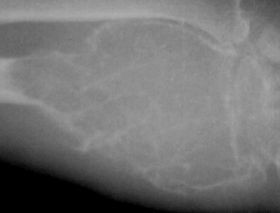

Első vizsgálati módszer a röntgenvizsgálat, mely általános képet ad a tumor határairól, méretéről, és arról, hogy a környező ízületet a tumor elérte-e. CT és MR képalkotó vizsgálatok adnak pontos képet a daganat körüli szövetek állapotáról. Szöveti (biopsziás) mintavétel után pedig a szövettan igazolja az oszteoklasztóma diagnózisát.